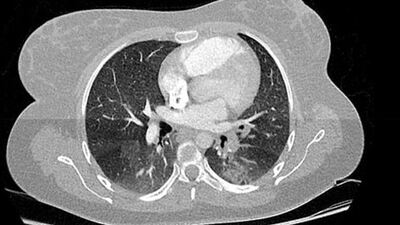

Dünyayı etkisi altına alan koronavirüs (Covid-19) salgını Avrupa'da can almaya devam ediyor. Fransız bilim insanları, 2019'un son aylarında çekilen binlerce göğüs filmi röntgenini incelemelerinin ardından koronavirüs (Covid-19) salgının Avrupa'ya Kasım ayında geldiğine yönelik bulguların bulunduğunu açıkladı.

Fransa'nın Haut-Rhin bölgesindeki Colmar kentinde bulunan Albert Schweitzer Hastanesi'nden Dr. Michel Schmitt ve ekibi, 2019´un son aylarında çekilen binlerce göğüs filmini incelerken koronavirüs ile benzer iki bulgu belirledi.

Dr. Schmitt ve ekibinin 16 - 18 Kasım 2019 tarihleri arasında çekilen göğüs filmlerini analizi sırasında yaklaşık 2 bin 500 röntgende koronavirüs bulgularına benzer bulgular rastlandığı ifade edildi. Sonuçların henüz çıkarılamayacağını ve ekibinin virüsün yayılmasını haritalamak için Ekim'e kadar uzanan X-ışınlarına bakacağını söyleyen Dr. Schmitt , "Geleceği ancak geçmişi anlarsak yönetebiliriz. Bugün bu salgını açıkça anlamıyoruz. Bu hükümetin yönetim stratejisini tamamen değiştirebilir" dedi.